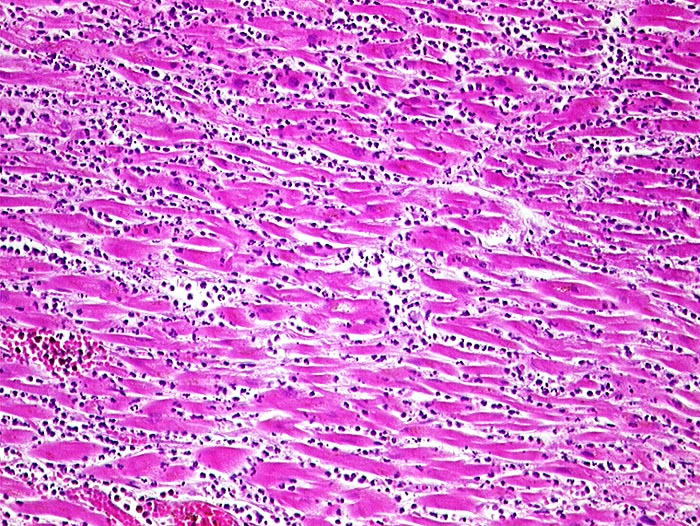

AP/ Akuter Myokardinfarkt

Akuter Myokardinfarkt

Morphologie

Pathologischer Befund